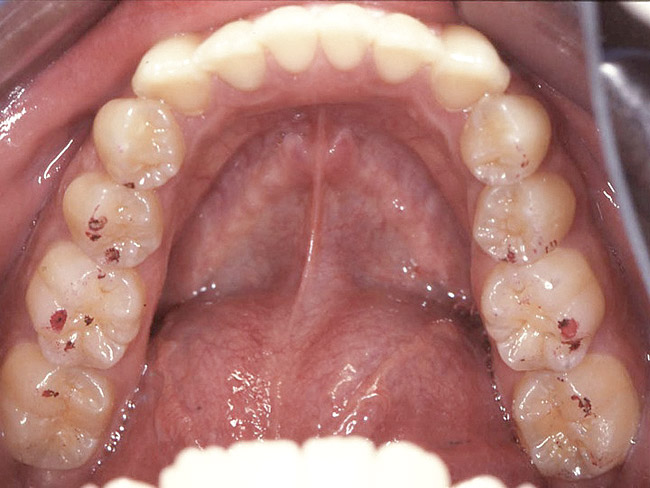

Loss of vertical dimension can be assessed through patient examination intraorally, extraorally, and functionally. Missing teeth and/or teeth worn from clenching or bruxing are the most common intraoral signs of a decreased VDO. Congenitally missing teeth can result in loss of vertical dimension with possible implications of compromised comfort, speech, and chewing (Figure 6 through Figure 8).

Figure 6. The patient is congenitally missing the maxillary lateral incisors and canines and all lower incisors and canines, causing concerns about esthetics. The maxillary laterals and canines and mandibular canines have been bonded with composite.

Figure 6

Figure 7. The mandibular incisors are loose, and No. 25 has recently been lost.

Figure 7

Figure 8. The lower one third of face seems shortened and the upper lip is not well supported and appears thin.

Figure 8